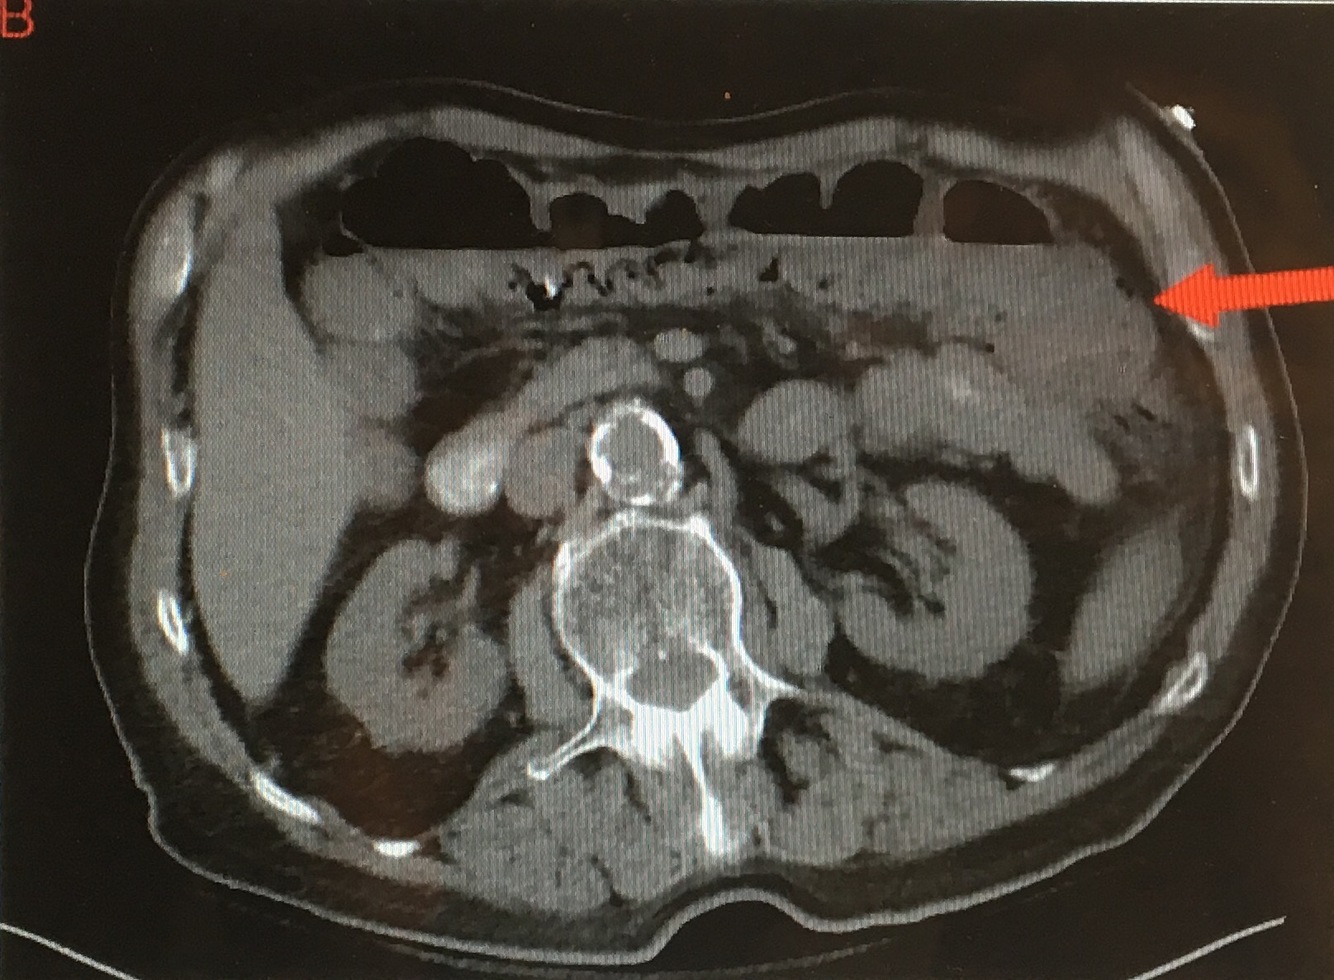

CT scan shows ______ which indicates _____. What causes this? Tx(2)?

[air in DEEP tissue]; Necrotizing Fasciitis;

[Group A Strep Pyogenes] (but typically polymicrobial) spreads rapidly thru SubQ & deep fascia after minor trauma –>

PAIN OUT OF PROPORTION WITH EXAM +

hypOtension +

[Erythema & Swelling]

Tx = Debridement + Broad Abx